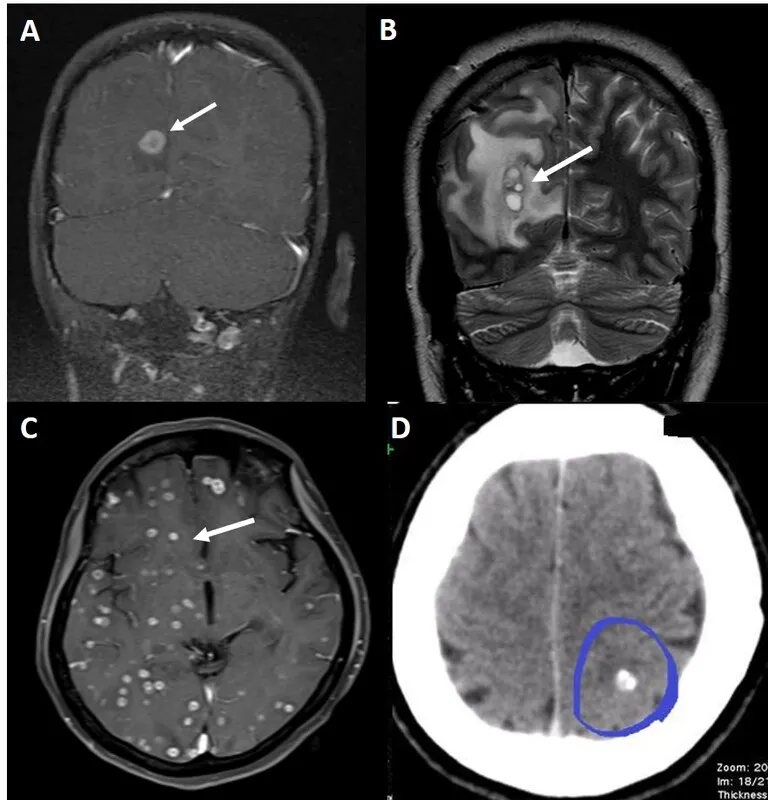

- Neurocysticercosis (NCC): T. solium larvae. Seizures. CT/MRI: cysts, scolex, calcifications. Rx: Albendazole + steroids.

⭐ NCC is the most common cause of adult-onset seizures in endemic areas like India.